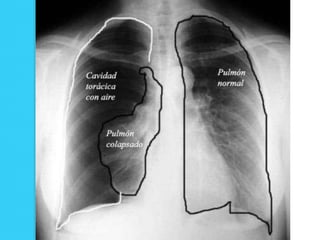

Se define al neumotórax como la presencia de aire en

la cavidad pleural el que proviene producto de una

lesión en el parénquima pulmonar, lo que con lleva un

colapso de este parénquima en mayor o menor grado

según sea la cuantía del neumotórax.

Un neumotórax grande el pulmón se colapsa totalmente

• El pulmón colapsado es muy denso y no hay trama

vascular en el hemitórax que rodea al pulmón.

Neumotorax pequeño  fina línea blanca de la pleura

visceral del pulmón

*Esta línea blanca se delimita centralmente por el aire

radiolúcido dentro del pulmón y periféricamente por el

aire dentro de la cavidad pleural.